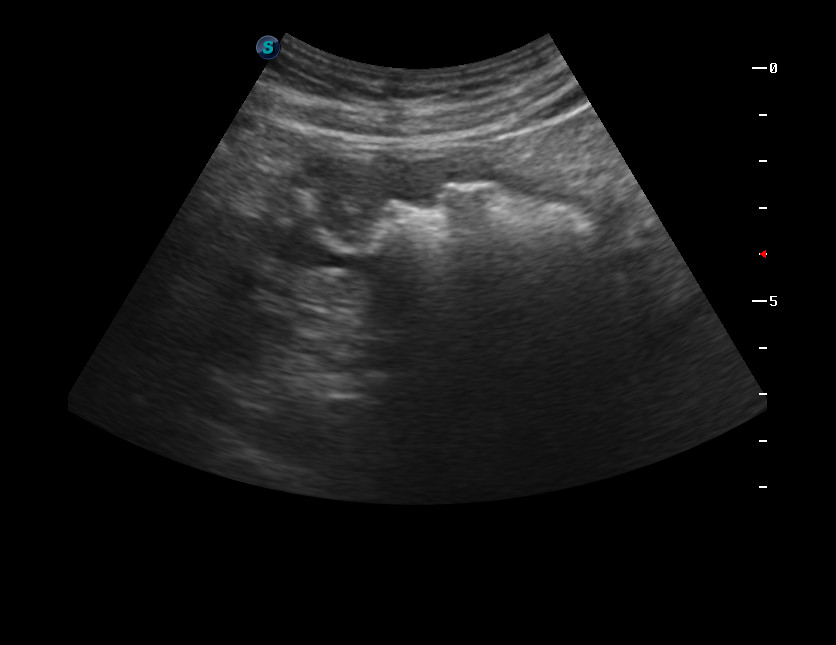

Дедушка 90 лет. Профилактическое обследование.

Выявлен сегмент толстой кишки с неравномерно утолщенными стенками.

После дообследование выполнена резекция толстой кишки, диагноз аденокарциномы подтвержден морфологически.